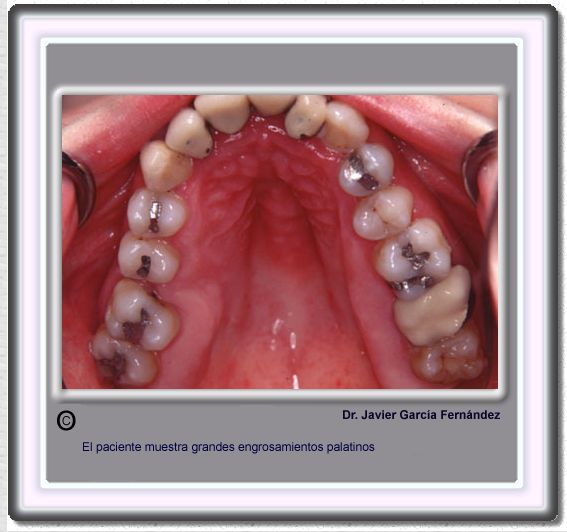

image 708